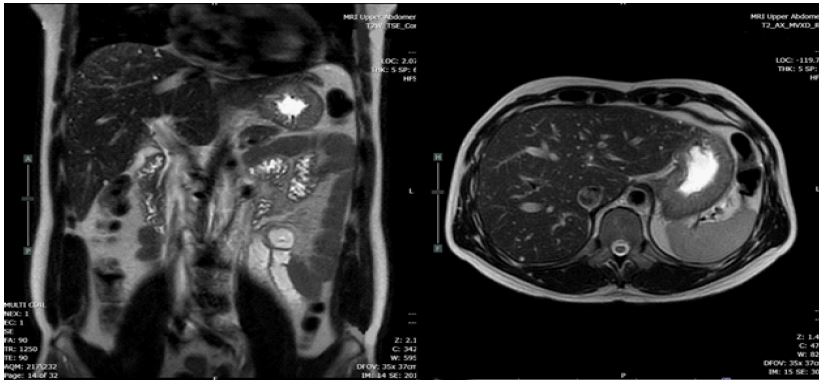

This patient was treated by medication; bronchodilator inhalator for symptomatic relief, molnupiravia (200 mg) 1 tab every 12 hours for 5 days. He was still complaining of fatigue and dyspnea. After failure of medication treatment, the electrocardiography and echocardiography were requested for re-evaluation. The result of that investigation showed normal. The CT chest was performed and reported innumerable Too Small to Characterize (TSTC) lesion scattering both hepatic lobes (Figure 1). The further Magnetic Resonance Imaging (MRI) revealed innumerable cystic lesion in both lobes of liver, (Figure 2). TW showed a signal lower than the liver parenchyma and T2W showed cystic hyperintensity like a ‘starry sky’ (Figure 3).

Figure 3: The MRI revealed innumerable cystic lesion in both lobes of liver like a ‘starry sky’.

VMCs usually do not cause symptoms and incidental finding with recent noninvasive imaging modalities. Most of biliary hamartoma are composed of small, 5-30 mm disorganized clusters of dilated cystic bile ducts that appear throughout the liver and generally do not communicate with biliary tree [8]. The CT scan of VMCs consists of multiple small, low attenuated areas that do not enhance on contrast injection. MRI of liver and MRCP show low signal intensity on T1-weighed and high signal intensity on T2-weighed images sequences give the liver a ‘starry sky’ appearance [9-11].